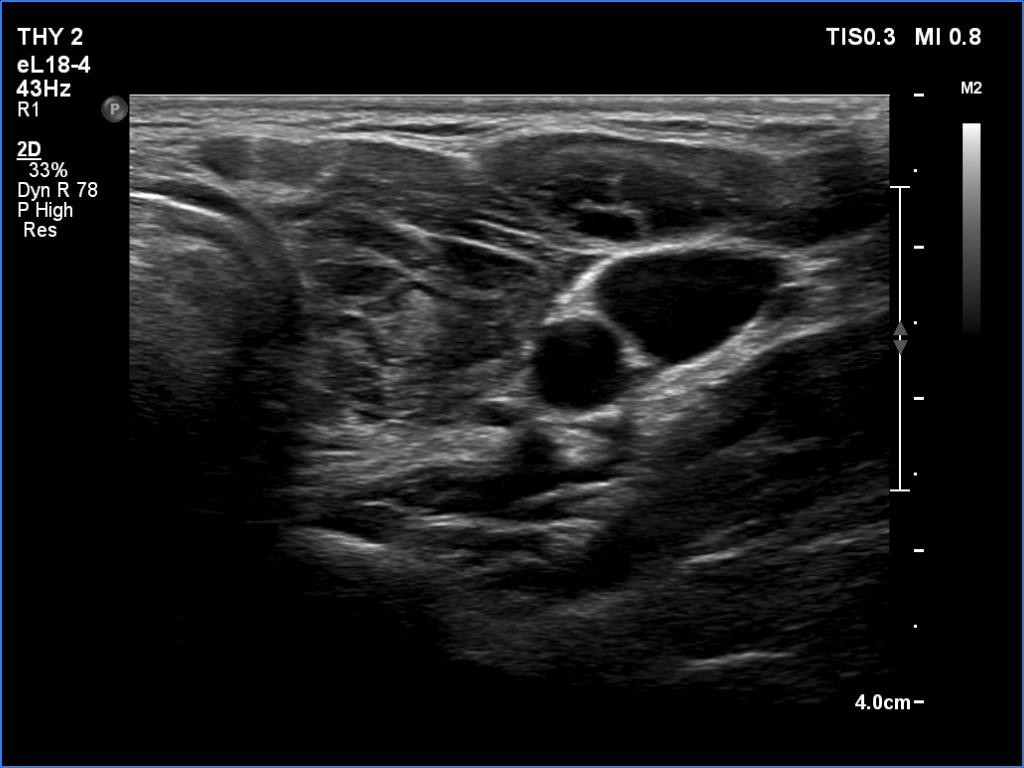

Ultrasonography. The thyroid was deeply hypoechoic and had numerous discrete iso/hyperechoic lesions. The latter had irregular shape and borders. The vascularity was increased. None of the discrete lesions corresponded to pathological nodules.